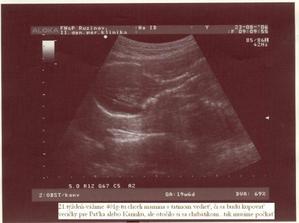

...žili dvaja šťastní ľudia, ktorým ale postupom času začalo niečo chýbať. Keď zistili čo, začalo sa krásne obdobie. Vyvrcholením tohto obdobia sa stal tretí človiečik 🙂, zatiaľ žijúci vo svojom vnútornom bezpečnom svete. Svetlo sveta by mal uzrieť začiatkom budúceho roka...